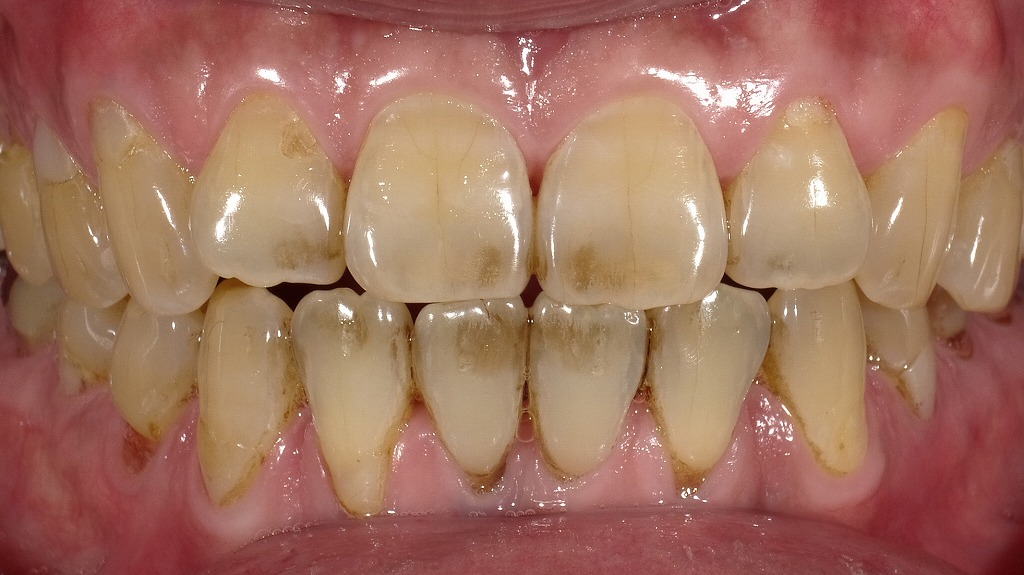

この写真は、上下の前歯を中心とした口腔内の正面画像です。歯の状態を観察すると、以下の特徴が見られます。

- 歯の全体的な色調:全体的に黄色味が強く、歯面に**茶褐色の着色(ステイン)**が目立ちます。特に下の前歯(下顎前歯)に多く付着しています。

- 原因の可能性:タバコ、コーヒー、紅茶、ワインなどの摂取、または歯磨き不足による外因性の着色(ステイン)と考えられます。

- 上顎前歯(上の前歯):中央2本(中切歯)および隣の側切歯に、歯の中央付近に茶褐色のステインが認められます。

- 下顎前歯(下の前歯):歯頸部(歯と歯ぐきの境目)にかけてステインが顕著で、歯石の沈着も疑われます。

- 歯肉(歯ぐき):全体的に健康的なピンク色ですが、下前歯の付け根付近はわずかに炎症傾向があるように見えます。

- ステイン(外因性着色):主に嗜好品による歯面への着色。歯の内部に色素がしみこんだ状態ではなく、表面に付着しています。

- 歯石の付着:特に下の前歯裏側や付け根部分に多く見られるため、歯科医院でのスケーリング(歯石除去)が必要です。

- エナメル質の摩耗:切縁(歯の先端)がややすり減っており、歯ぎしりや加齢変化の影響も考えられます。